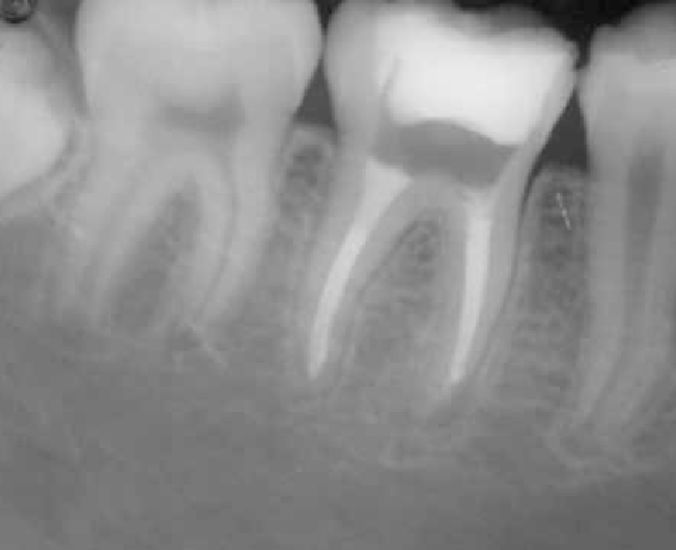

Lesões no Periápice

Tratamento de lesões no periápice e eliminação de foco de infecções (medicação intracanal).